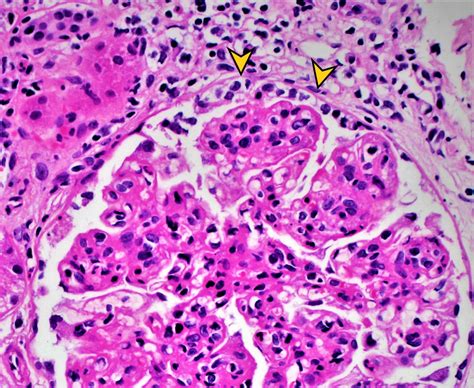

RPGN is a syndrome rather than a single disease, encompassing a group of conditions that cause rapid and severe damage to the glomeruli. The primary feature of RPGN is the presence of crescents in the glomeruli, which are composed of cells that accumulate in the Bowman's space, leading to the destruction of the glomerular structure. This process impairs the kidney's ability to filter blood, resulting in a rapid decline in renal function.

• Kidney Biopsy - A definitive diagnosis often requires a kidney biopsy to examine the glomeruli under a microscope. The biopsy can reveal the presence of crescents and help determine the type of RPGN.